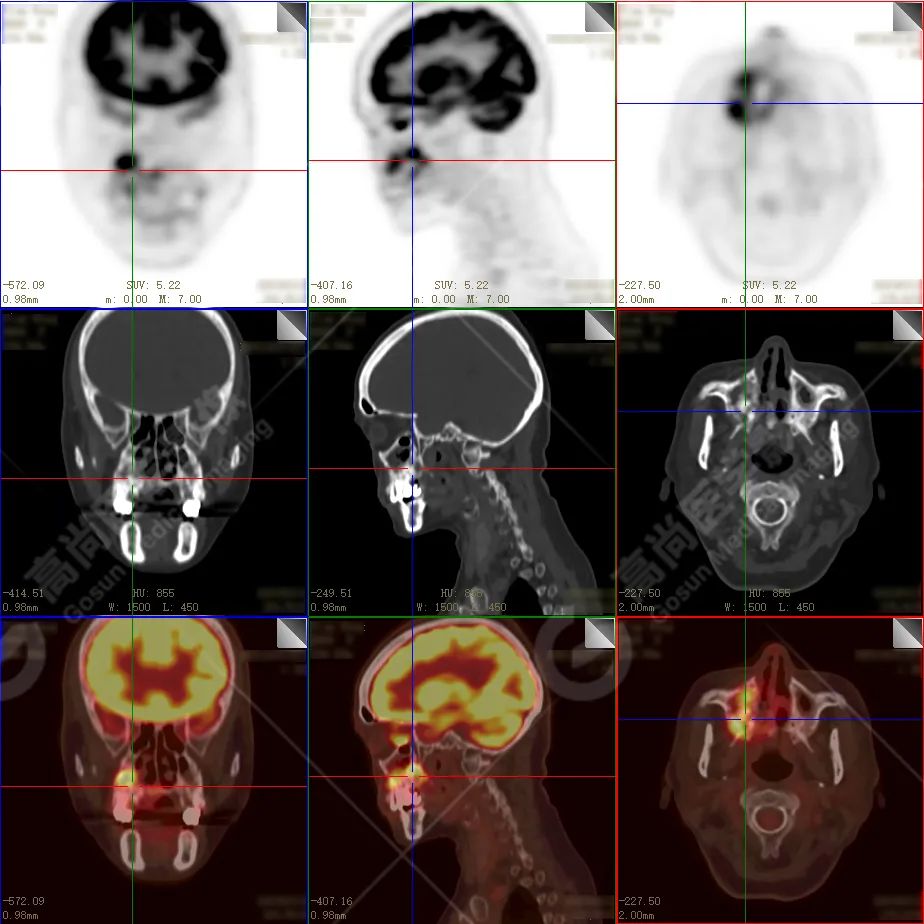

右侧上颌骨-上颌窦骨壁-骨性鼻中隔区域见片块状放射性摄取异常增高影,最大层面约 4.1 cm×3.8 cm×2.8 cm,SUV 最大值为 10.4,CT 示上述部位见成骨性改变,骨质不均匀弥漫性增厚、密度不均匀增高,并可见肿瘤骨影,边缘毛糙,周围伴软组织增厚。

根治性手术在放疗后骨肉瘤的治疗中是必须的,然而根治性手术仅仅适用于早期的病例,如本例病人,相对早期,周围组织结构无明显侵犯,PET 示肿瘤代谢也局限于肿瘤本体。